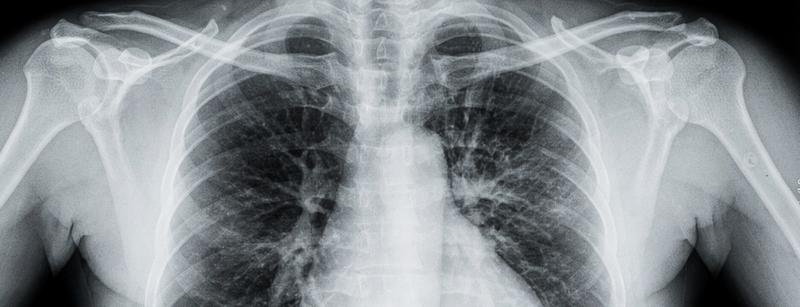

- Вирус поражает эпителий бронхов и легких, нередки случаи вторичной пневмонии.

- Вирусная пневмония из-за поражения альвеолярного эпителия.

- Бактериальная пневмония, которая развивается при проникновении бактерий через поврежденные участки слизистой.

- Острый респираторный дистресс-синдром (ОРДС) — тяжелое диффузное поражение легких с нарушением газообмена.

- Обструктивный бронхит — воспаление бронхов с сужением их просвета из-за отека слизистой и скопления вязкой мокроты.

- Обострение хронической обструктивной болезни легких на фоне воспалительного процесса.